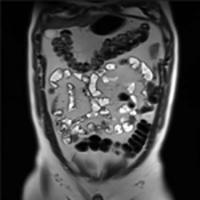

All centres within the Calgary Region involved in fellowship training house state-of-the art imaging infrastructure in all modalities, perform a large number of studies and are involved in both clinical and research endeavors.

Pediatric radiology fellowship programs are based primarily at Alberta Children’s Hospital, the tertiary care referral centre for children for Southern Alberta, Southwestern Saskatchewan and Southeastern British Columbia where both diagnostic and interventional procedures are performed.